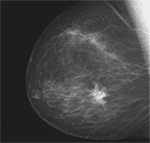

El uso de esta tecnología disminuye los efectos adversos de la mamografía de cribaje, ya que evita que muchas mujeres se sometan a nuevas pruebas de diagnóstico innecesarias, algunas invasivas como las biopsias.

El estudio, en el que han participado investigadores del Servicio de Epidemiología y Evaluación y de Radiología del Hospital del Mar y de los programas de detección precoz de cáncer de mama de Gerona, Cantabria y Valencia, ha confirmado que la introducción de la mamografía digital (MD) en los programas de detección precoz de cáncer de mama reduce el número de resultados falsos positivos y, consecuentemente, el número de mujeres que tienen que hacerse más pruebas cuando no hay cáncer.

Esta investigación, publicada en la revista Radiology, contrasta la eficacia de la mamografía digital (MD) contra la mamografía convencional y demuestra que cuando hay un tumor ambas pruebas lo detectan por un igual, pero en casos en que la imagen puede parecer un cáncer sin serlo, la MD afina más el diagnóstico y reduce así los resultados falsamente positivos y en consecuencia, la angustia de las mujeres al no tener que hacerse otras pruebas como ecografías o biopsias, y a su vez, hace más eficientes los programas de cribaje de cáncer de mama al disminuir el gasto.

La investigación, liderada por la doctora María Sala del Hospital del Mar, se ha desarrollado a partir del análisis de un total de 242.838 mamografías de cribaje (171.191 por técnica analógica; 71.647 por método digital) de cuatro programas de detección precoz de cáncer de mama de Barcelona, Gerona, Valencia y Cantabria. En el examen, realizado entre 1996 y 2007, han participado un total de 103.613 mujeres de entre 45 y 69 años. “En total, se han diagnosticado 1.080 cánceres sin diferencias significativas entre mamografía analógica y digital, pero hemos observado que el porcentaje de pruebas innecesarias ha sido inferior con la MD”, señala la investigadora María Sala. Estas conclusiones derivan de un proyecto mucho más amplio y multicéntrico, coordinado desde el Hospital del Mar por el Dr. Xavier Castells, Jefe del Servicio de Epidemiología, donde participan los Programas de detección precoz más consolidados del país.

Una elevada proporción de tumores se diagnostican a partir de las mamografías de cribaje que se realizan cada dos años a las mujeres que participan en los programas de detección precoz. En este sentido, la mamografía digital ha demostrado disminuir pruebas innecesarias como biopsias o ecografías en mujeres que no tienen cáncer. Ahora bien, ¿qué pasa cuando el cáncer aparece entre este intervalo de tiempo, es decir, entre una mamografía y otra? “En algunos casos, cuando la mujer se hace la mamografía no hay presencia de tumor; pero antes de hacer la siguiente mamografía, ya existe”, explica la investigadora María Sala. Estos tipos de tumores se conocen como “verdaderos cánceres de intervalo”, tumores de mama de crecimiento rápido, que en una elevada proporción presentan un patrón molecular asociado a un peor pronóstico -llamado cáncer triple negativo-y más frecuentes en mujeres con elevada densidad mamaria, según muestra un estudio reciente de este mismo equipo del Hospital del Mar, en colaboración con el Servicio de Oncología y Anatomía patológica, publicado en la revista Cancer Causes Control. Las características de estos tumores los hace menos susceptibles de ser detectados en las pruebas de cribaje. Es por este motivo que “es necesario profundizar en el estudio de los determinantes que condicionan la aparición de estos tipos de cáncer –señala la Dra. Sala- para, en un futuro mejorar la eficacia del proceso de cribaje, a partir de la revisión de los intervalos entre mamografías, en función de los patrones de riesgo de las mujeres o haciendo uso de diferentes tecnologías (como las resonancias magnéticas) para grupos específicos de mujeres”.